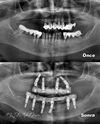

Implant tedavisi